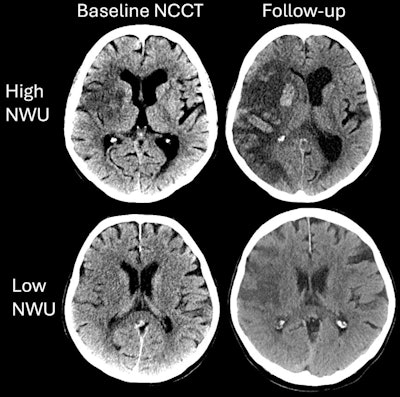

Axial noncontrast CT (NCCT) images in patients in The Efficacy and Safety of Thrombectomy in Stroke with Extended Lesion and Extended Time Window (TENSION) trial who underwent endovascular thrombectomy with low versus high ischemic lesion attenuation. The two cases highlighting differences in relative hypoattenuation in patients included in the TENSION trial. Patient 1 (upper row) was a 74-year-old female with acute ischemic stroke due to a proximal occlusion of the right middle cerebral artery, NCCT, axial plane; no contrast used. Baseline Alberta Stroke Program Early CT Score (ASPECTS) was 5, with high net water uptake (NWU). Patient 2 (lower row) was a 68-year-old male with acute ischemic stroke due to a proximal occlusion of the right middle cerebral artery; NCCT, axial plane; no contrast used. Baseline ASPECTS was 3, with low NWU. The patient with high NWU (upper row) died despite successful endovascular treatment. The patient with low NWU (lower row) achieved functional independence (modified Rankin scale score of 2). Images and caption courtesy of the RSNA.